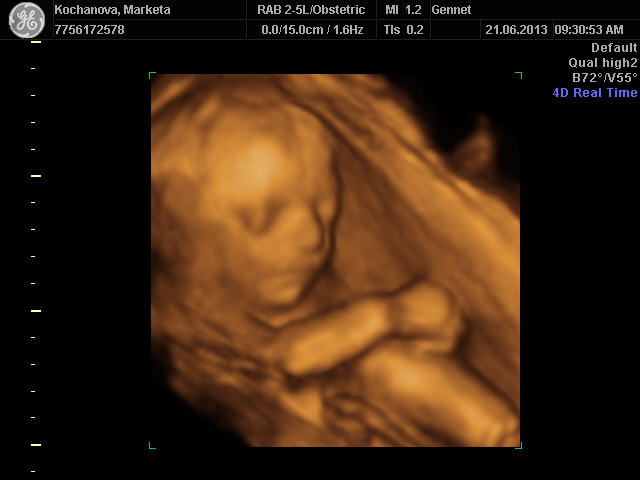

Markytanko,

moooc hezká slečna :-) Máš hezčí fotečku, u nás byl Matěj zádíčkama, takže mam na fotce bok, kolínko a loket...